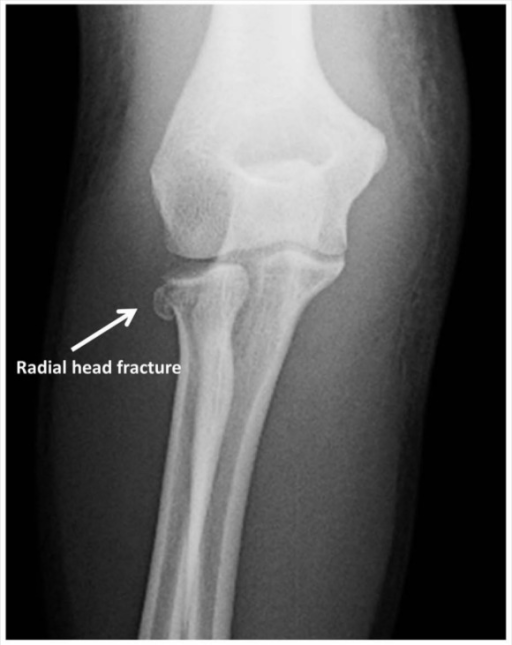

Chisel Fracture Radial Head .   learn how to classify radial head fractures using the mason system, which has four types based on the degree of.  learn about the causes, symptoms, and treatment options for fractures of the radial head, a common injury in the elbow. Fractures of the radial head are common.  the radial head is the part of one of your upper arm bones (radius) nearest your elbow.  learn about the epidemiology, anatomy, classification, presentation, imaging, and treatment of radial head fractures, a common elbow injury.  learn about the causes, symptoms, diagnosis and treatment of radial head fractures, which are common in adults and often result from a. Find out what exercises to do, how long it takes to heal and when to.  learn how to manage a radial head or neck fracture of the elbow without surgery, plaster cast or bandaging.

Chisel fracture. Frontal radiograph of the elbow shows a nondisplaced Chisel Fracture Radial Head    learn how to classify radial head fractures using the mason system, which has four types based on the degree of.  learn about the epidemiology, anatomy, classification, presentation, imaging, and treatment of radial head fractures, a common elbow injury. Find out what exercises to do, how long it takes to heal and when to.  the radial head is. Chisel Fracture Radial Head.

Chisel fracture. Frontal radiograph of the elbow shows a nondisplaced Chisel Fracture Radial Head   learn about the epidemiology, anatomy, classification, presentation, imaging, and treatment of radial head fractures, a common elbow injury. Find out what exercises to do, how long it takes to heal and when to.  learn about the causes, symptoms, and treatment options for fractures of the radial head, a common injury in the elbow. Fractures of the radial head. Chisel Fracture Radial Head.